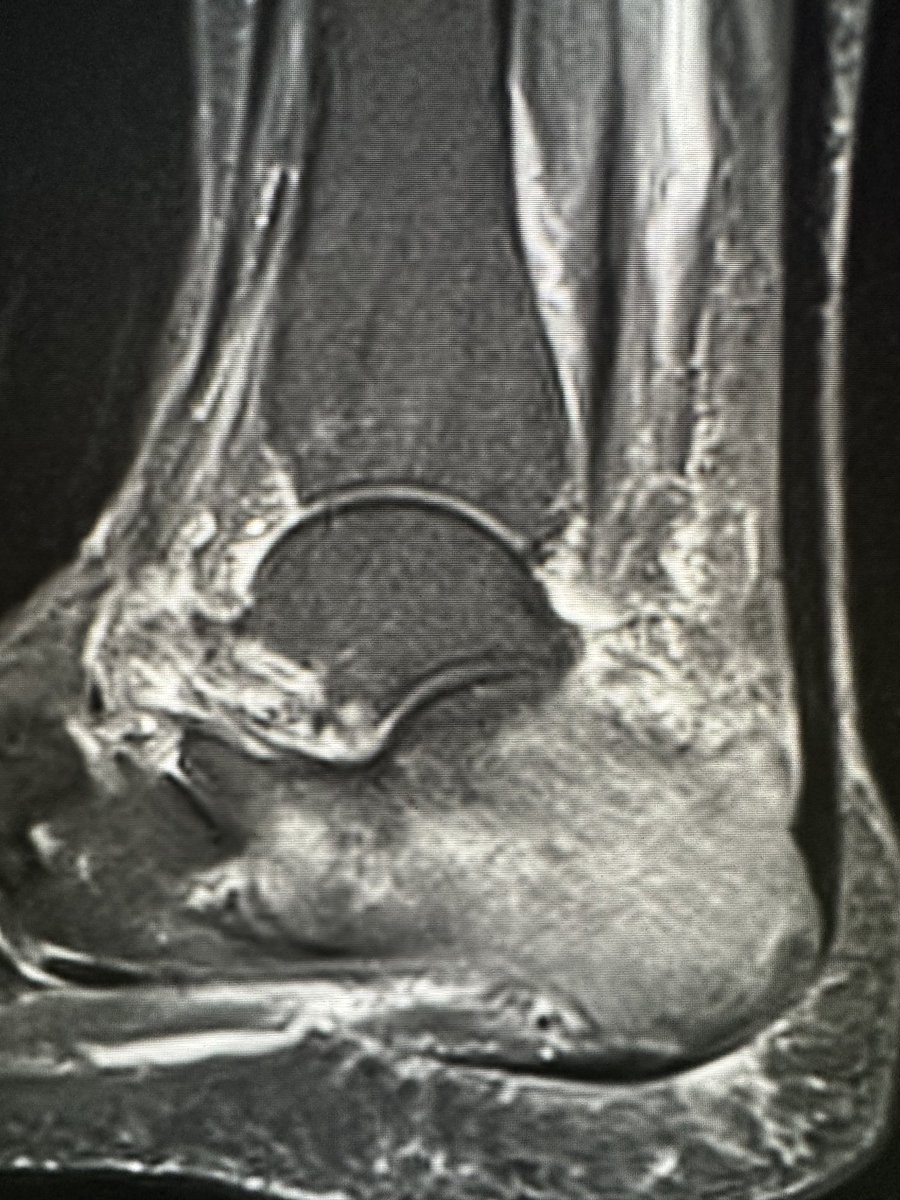

Nice example of a haglund deformity, insertional tendinopathy and partial tear with reactive bursitis

RJ tweet mediaRJ tweet media